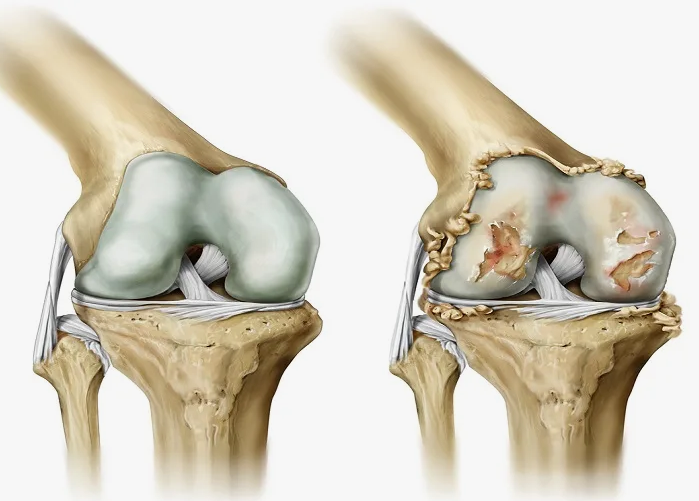

В случае перелома шейки бедра компания МосРентген Центр госпитализирует в Склиф для эндопротезирования.